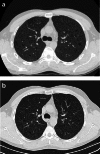

Objectives: Pulmonary Langerhans cell histiocytosis (PLCH) is a rare interstitial granulomatous disease that usually affects young adults who are smokers. Chest computed tomography (CT) allows a confident diagnosis of PLCH only in typical presentation, when nodules, cavitated nodules and cysts coexist and predominate in the upper and middle lungs.

Methods: This article includes a pictorial essay of typical and atypical presentations of PLCH at initial chest CT. Various appearances of PLCH are illustrated and possible differential diagnosis is discussed.

Results: PLCH can present with some aspecific features that may cause diagnosis of the initial disease to be overlooked or other pulmonary diseases to be suspected. In cases of nodule presentation alone, the main differential diagnosis should include lung metastasis, tuberculosis and other infections, sarcoidosis, silicosis and Wegener's disease. In cases of cysts alone, the most common diseases to be differentiated are centrilobular emphysema and lymphangiomyomatosis. Clinical symptoms are usually non-specific, although a history of cigarette smoking, coupled with the presence of typical or suggestive findings at imaging, is key to suspecting the disease. Atypical presentations require surgical biopsy for diagnosis.